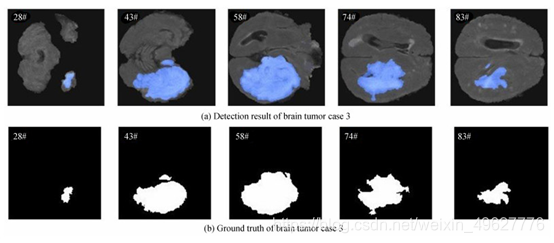

从脑肿瘤测试集中任选3个病例样本进行检测结果可视化分析,图 17~19分别为3个病例中5个序列的检测结果,以及对应序列的脑肿瘤病灶金标准图.

图 19 脑肿瘤病例3结果图

从图 17~19可以看出,设计的多模态脑肿瘤病灶检测方法所得到的检测结果,与金标准拟合程度高,说明该方法可有效检测出MRI脑部影像中脑肿瘤病灶.